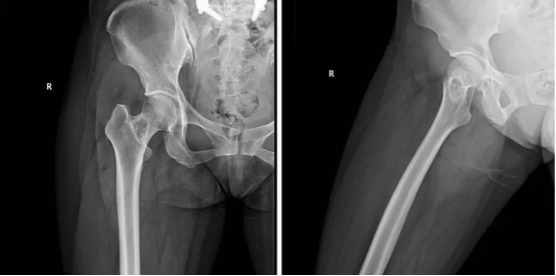

股骨近端包括股骨头、股骨颈以及股骨的粗隆部,是良性肿瘤尤其是瘤样病变的好发部位。主要以孤立性骨囊肿、骨样骨瘤、纤维结构不良等为主。良性肿瘤或肿瘤样病变是最常见的偶然发现的病变,在许多情况下,这些被称作为“沉默的病变”仅需要监视,而不是手术。不过作为负重关节的一部分,股骨的近端需要承受垂直应力及剪切应力,当这些病变位于股骨近端时容易产生病理性骨折,因此手术治疗往往是首选。而传统的手术方式包括刮除植骨内固定、骨水泥填充,极端的情况采用股骨近端关假体置换等,创伤较大,远期并发症如股骨头坏死、局部疼痛.松动翻修等,一直是骨肿瘤医生比较忌惮的手术部位。